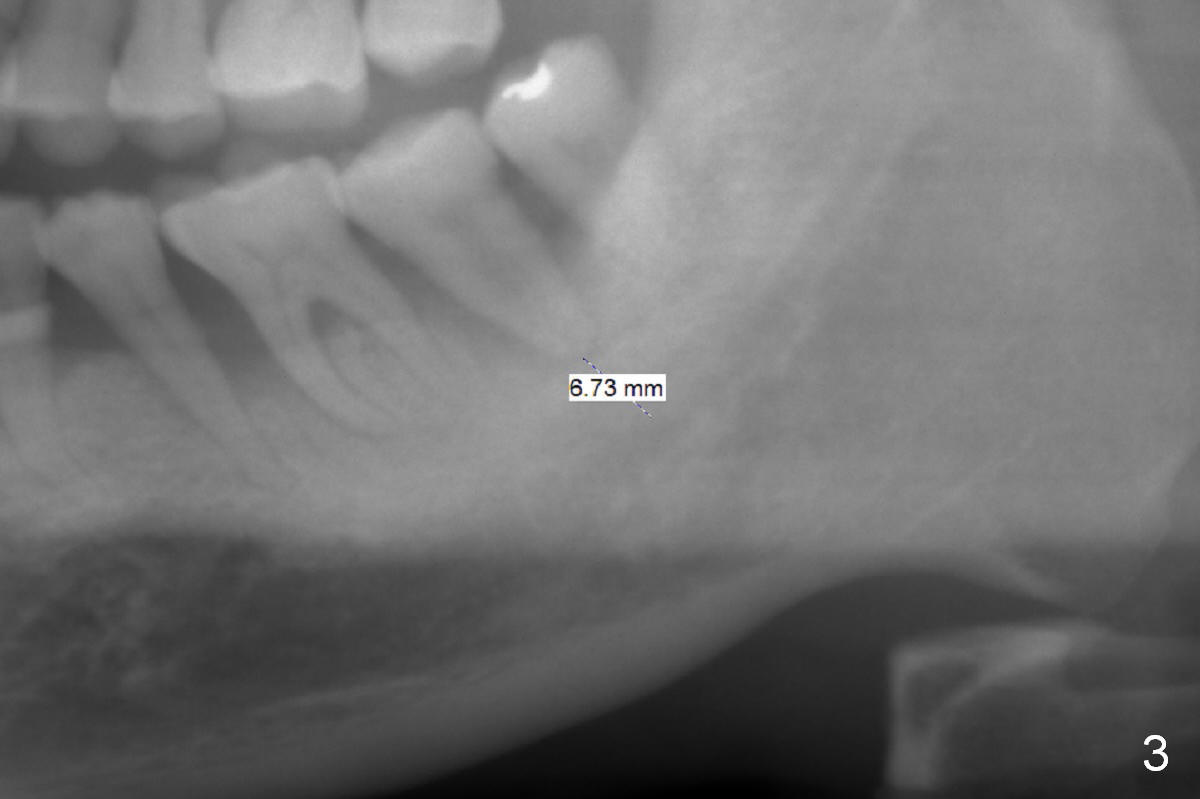

The teeth #14 and 18 of a 46-year-old man become symptomatic 1 month after #4 implant placement. While the socket at #14 is shallow, the apical bone is abundant (Fig.1). The longest IBS implant should be safe (13 mm, Fig.2). In contrast, the socket at #18 is relatively deep, the apical bone is short (Fig.3). A shorter implant (11 mm or less, Fig.4) should be chosen. Osteotomy in the new bone should be 4 mm. Try in a 5x9 mm dummy implant at #18. No antibiotic is used for socket treatment. The bone density in the mandible should be high (drills), whereas that in the maxilla may be low (expanders) or medium (drills). Preop exam will decide which tooth needs treatment first. Take photos PRN.